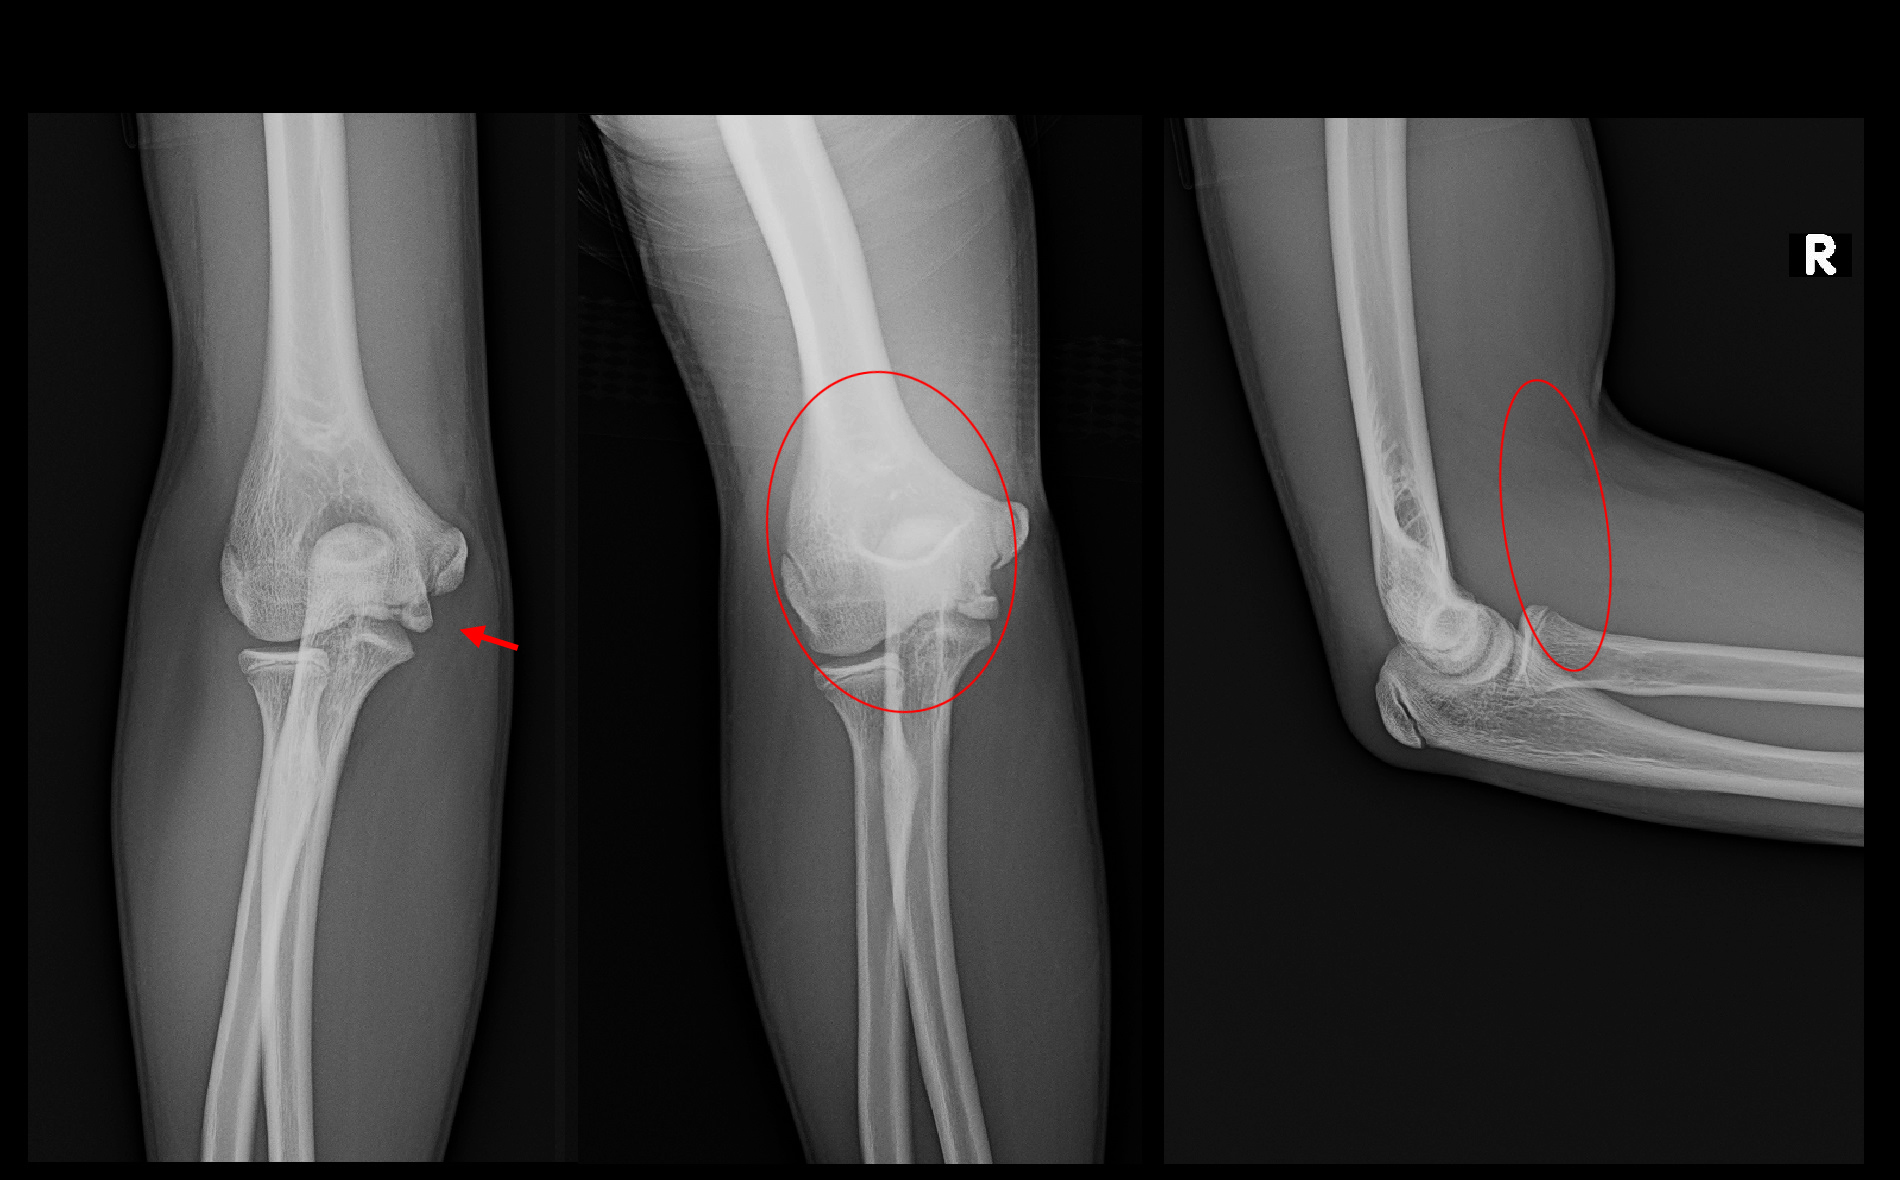

13才男 Xp2.jpg

受傷後4週の3月27日のレントゲン像では上腕骨内顆部(上図の拡大図の領域です)は、初診時には確認できなかった骨透亮像(透明化=黒っぽくなった所見/赤矢印の領域です)が確認でき、これは骨の壊れが進んだ所見です。しかし、骨透亮部は肉が固まってきている状態で痛みは軽減してきています。この時点でギプスシーネは除去しています。

13才男 Xp3.jpg

4月10日(初診6週後)日常生活での痛みはなくなり、剣道の練習開始を許可しました。

4月28日(初診2か月後)剣道を100%で行っているが、痛みはVAS2程度であるとのことでした。レントゲン像でも骨透亮部位には骨形成が起きて、白くなってきています。この時点で経過観察は終了としました。